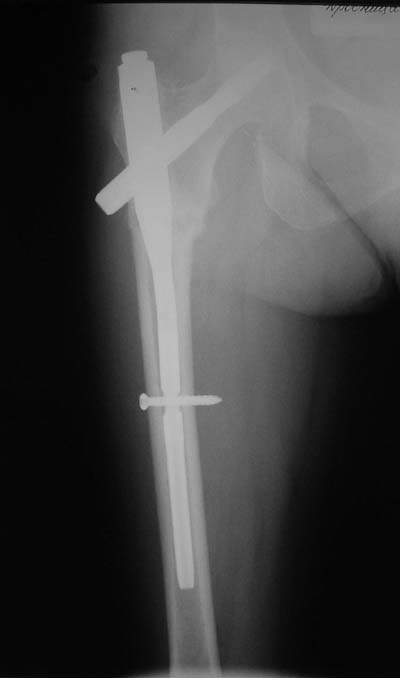

Да? Качество рентгенограмм конечно неочень, но ведь это нестабильный перелом 31.А2.2, не так ли?

Не думаю так. см вложение.

> Не думаю так. см вложение.

Для такого перелома вполне может быть использован диафизарный штифт, который отечественного производства я даже боюсь считать во сколько раз дешевле... Недавно несколько примеров я закидывал.